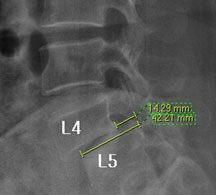

모커리한방병원 표○○ (57, 여) 척추전방전위증 2단계 실제치료사례 이미지

표○○ (57, 여) 척추전방전위증 2단계 입원치료기간 : 20일

입원시 퇴원시

허리 통증지수(NRS) 8 0

엉덩이 통증지수(NRS) 7 0

통증없이 걷는거리(m) 10분

(약 10분 앉은 자세를

유지시 통증 발생)

30분

(약 30분 보행 후 가벼운

통증, 입원 첫날에 비하여

통증 20~30%로 감소)